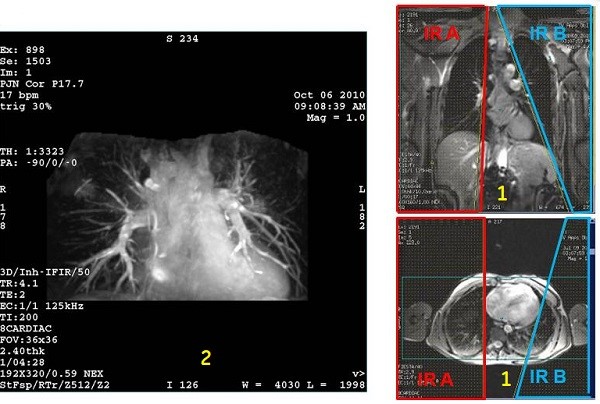

• Pulmonary arteries

Figure 10. Coronal localizer with IR band and resultant coronal pulmonary arteries

Table 8. Image legend

NumberDescription

1Top localizer image: Coronal localizer with IR two bands applied over the lungs.

Bottom: Axial localizer with two IR bands applied over the lungs.

2Resultant Inhance Inflow IR coronal image of pulmonary arteries.